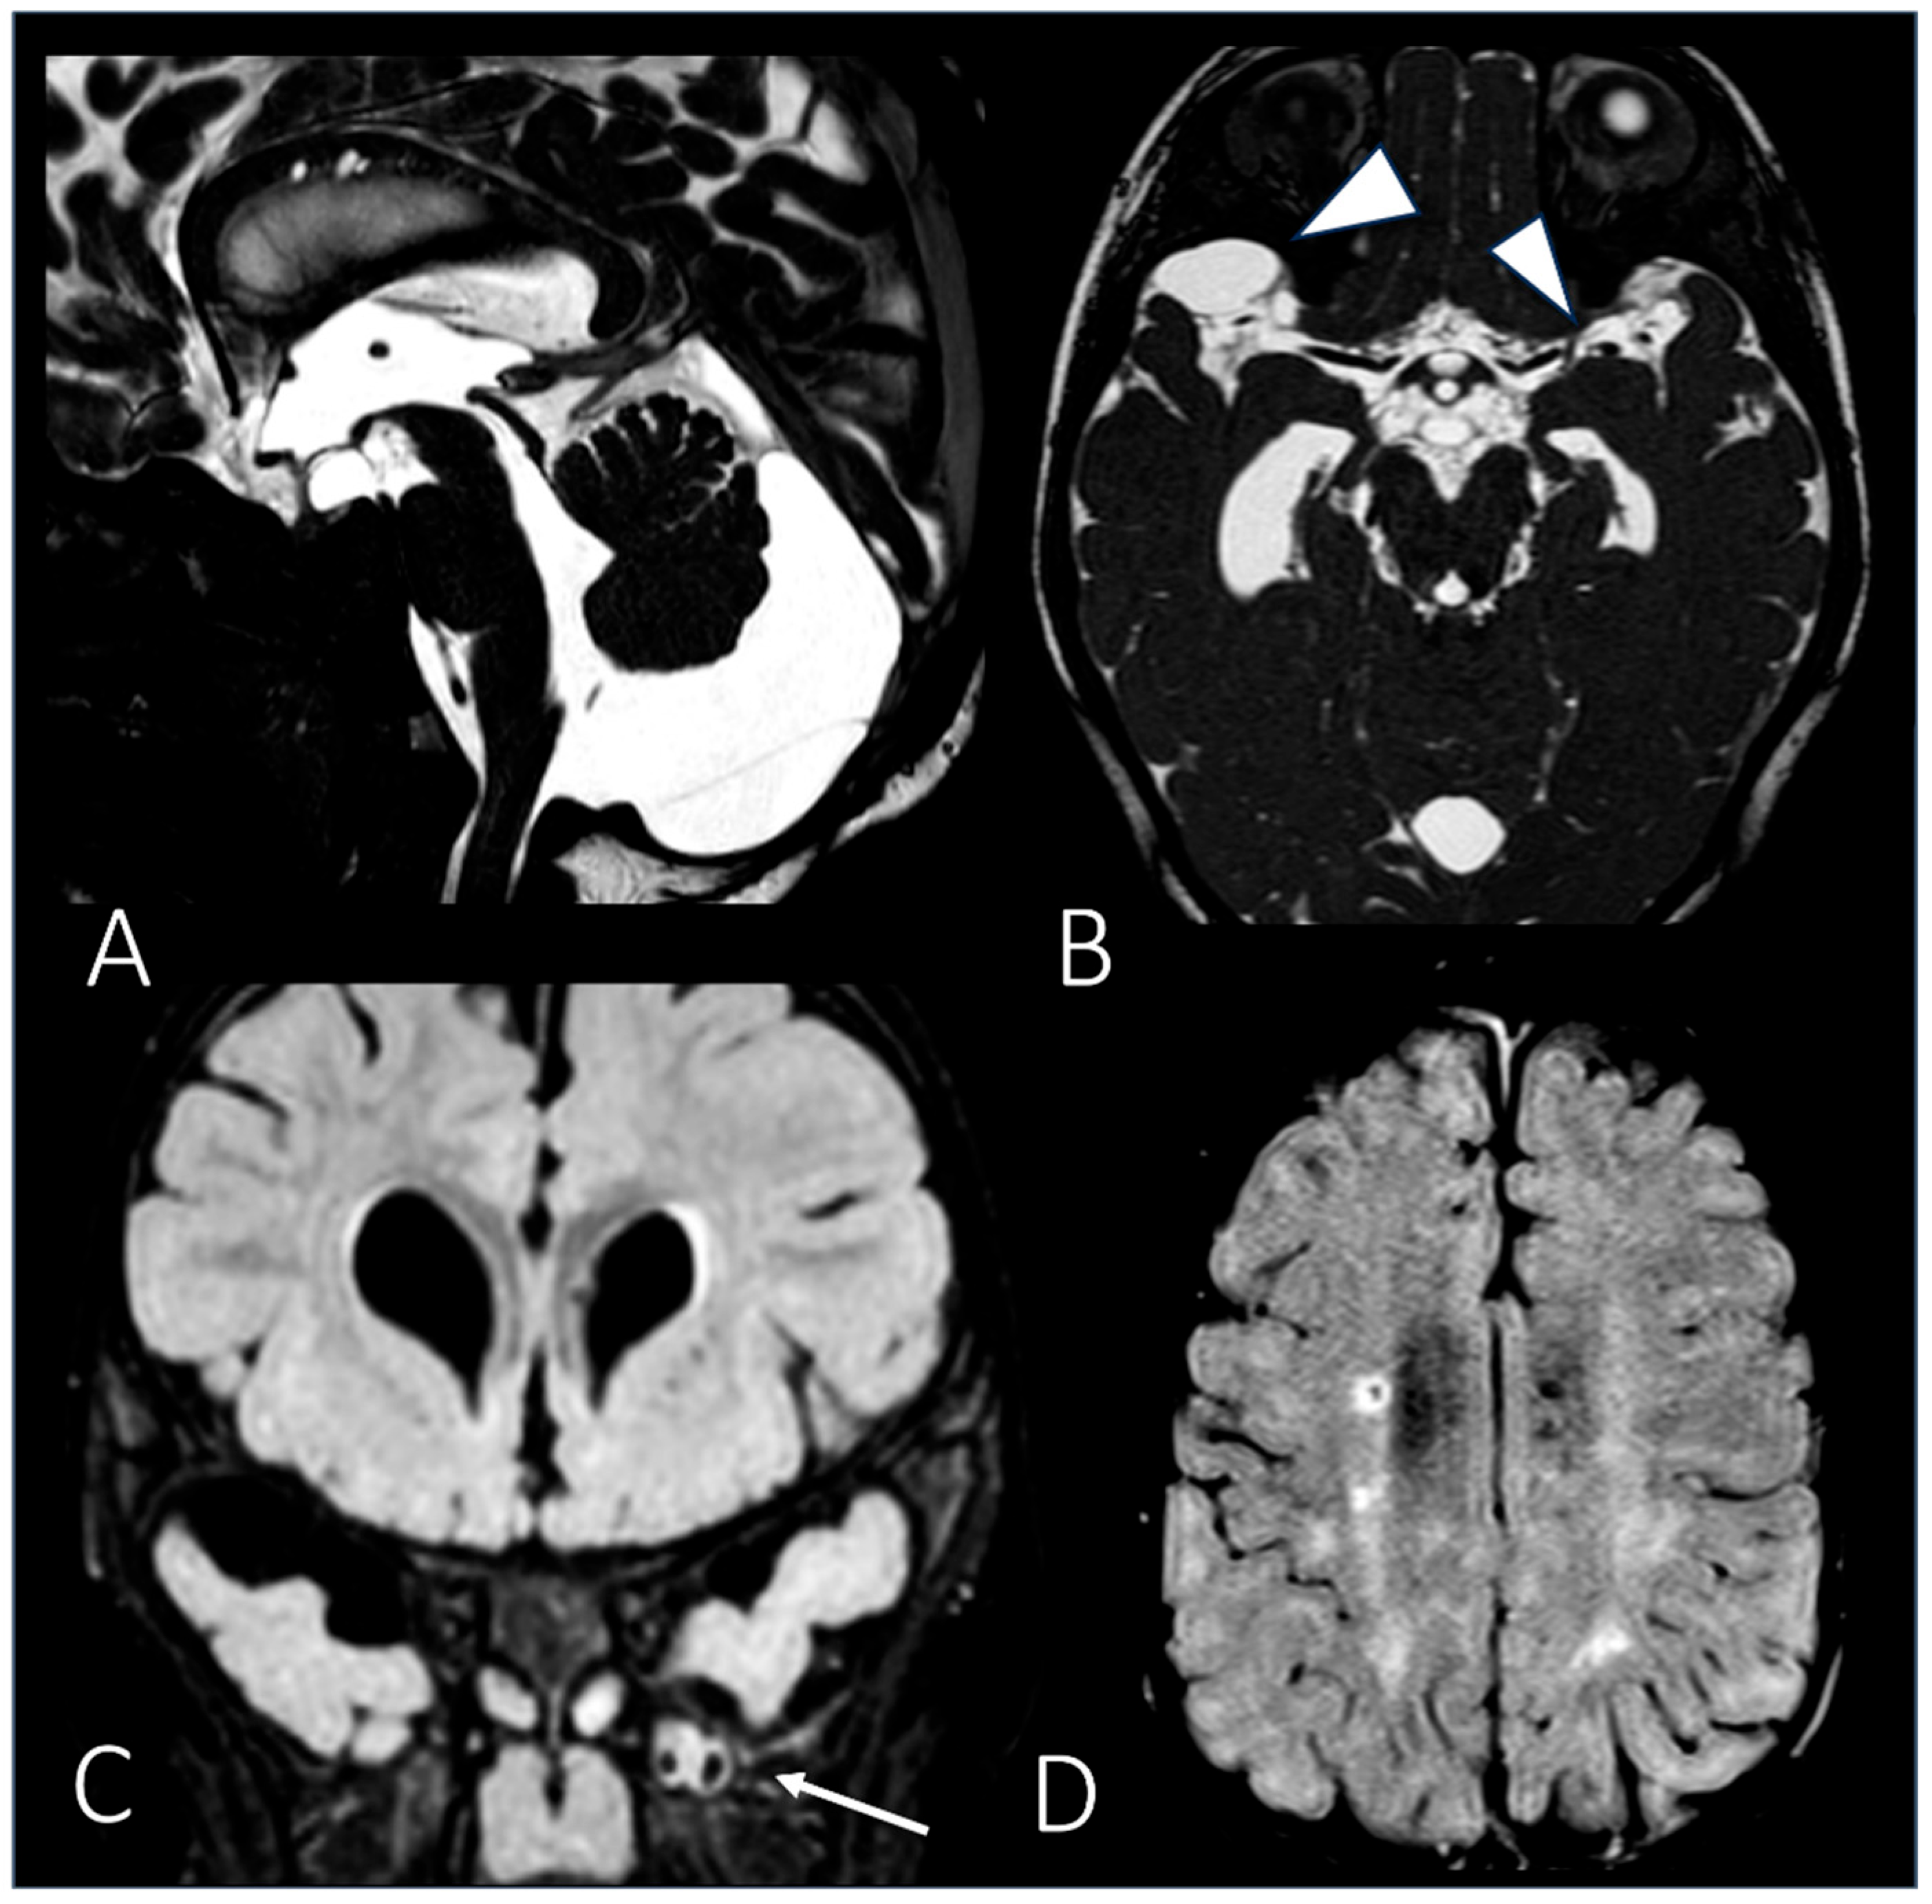

| MRI | Brain | Periventricular white matter abnormalities associated with enlarged perivascular spaces. | ||

| MRI | Brain | Extension of the white matter signal alterations; severe dilation of the ventricular system; cerebral atrophy. | ||